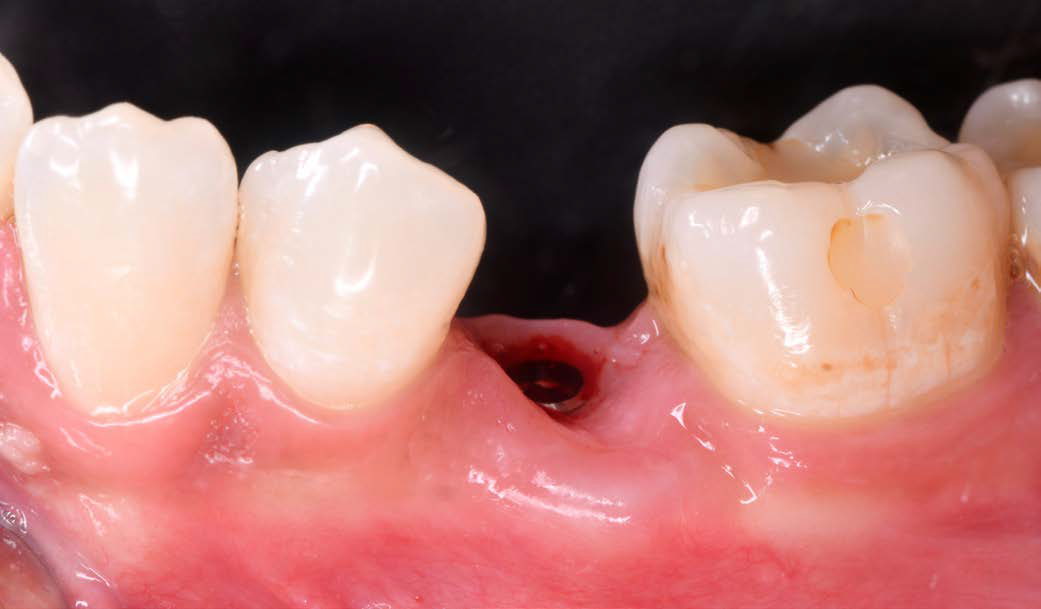

Figure 3: Condition after extraction and preservation of the buccal root portion |

A 26-year-old female patient was referred to my practice. Tooth 35 was deemed non-restorable. A CBCT scan showed the buccal bone plate was missing. Especially in aesthetic zones, we aim to reduce tissue collapse post-extraction (up to 50%). We considered various ridge preservation techniques to minimize this risk.

I chose the Socket Shield Technique, a minimally invasive method to reduce tissue shrinkage and achieve better long-term aesthetic outcomes. The technique requires healthy periodontal tissue and an intact root, both of which were present. The tooth is partially extracted, leaving the buccal root portion to support the soft tissue. This maintains the buccal periodontal attachment, allowing the tissue to behave as if the tooth were still in place. Hürzeler et al. introduced this technique in 2010 to reduce tissue shrinkage during immediate implantation.

Figures 7 and 8: Clinical situation after 6 months